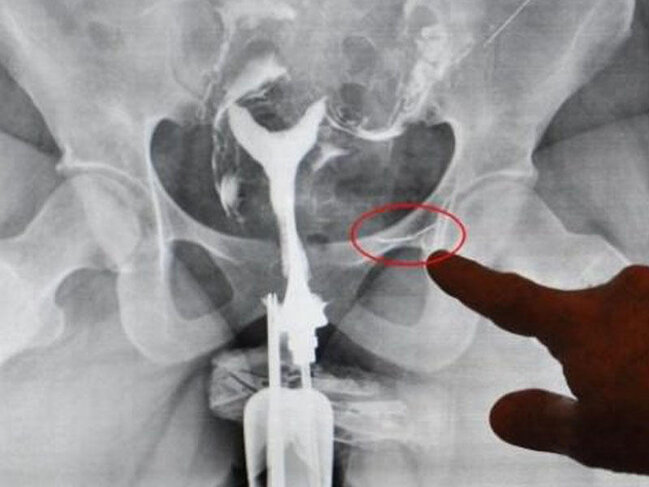

7News.Az dha-ya istinadən xəbər verir ki, rentgenə salınan qadının sidik kisəsinin xarici səthinə yapışmış tikiş iynəsi aşkar edilib.

38 yaşlı S.Ş. uşaq sahibi olmaq üçün üz tutduğu xəstəxanadan tikiş iynəsiylə yaşadığını öyrənib. Əməliyyata götürülən azərbaycanlı qadının sidik kisəsinə yapışmış iynə çıxarılıb. S.Ş. açıqlama verərək, "22 yaşımda səhvən iynə uddum. Tez xəstəxanaya getdik. Mənə həkimlərin çoxlu kartof yeyəcəyim təqdirdə iynənin özünün çıxacağını dedilər. Bir müddət sonra yenidən xəstəxanaya getdim. Həkimlər iynənin bədənimdən çıxdığını dedilər. Mən də həyatıma davam etdim. Qarnım tez-tez bərk sancırdı" deyib.

Həkim iynənin həyati orqanları zədələmədiyini bildirib.